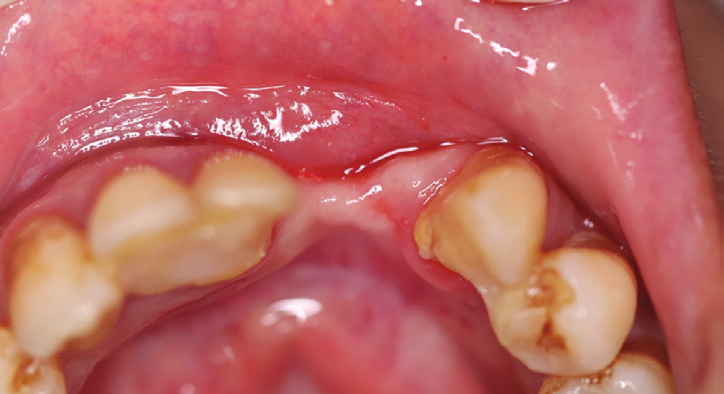

Figure 2: Intraoral view showing the extended bone and gingival loss with recession on both central incisor and canine.

Figure 3: Occlusal intraoral view showing the advanced amount of bone loss.

Intraoral examination showed a bridge replacing sites no 26 and 25 with a gingival extension replacing the bone loss in the area (Fig.1). Extra oral examination was normal.

After removal of the bridge an extended bone loss was found. (Fig.2, 3). X-rays and CAT views were taken for the region. The amount of bone loss was extended which was an indication for autologous bone graft. A PRF associated bovine bone technique was planned. A linear incision with mucoperiosteal flap elevation was conducted. The adjacent teeth showed also bone loss (Fig.4).